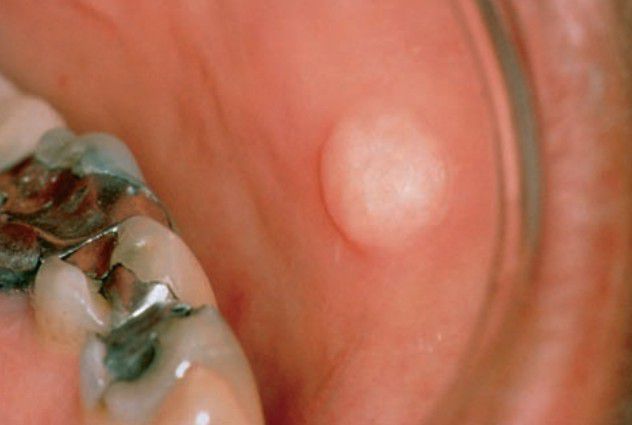

Focal fibrous hyperplasia

Focal fibrous hyperplasia is a reactive lesion usually caused by chronic trauma to oral mucous membranes. Overexuberant fibrous connective tissue repair results in a clinically evident submucosal mass.